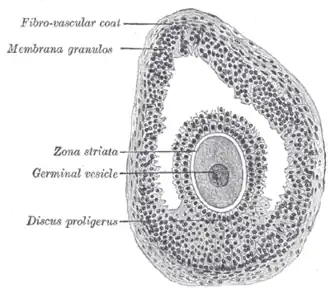

.jpg) Histology section of a mature ovarian follicle. The oocyte is the large, round, pink-staining cell at top center of the image. | |

Once a month, one of the ovaries releases a mature egg (ovum), known as an oocyte. The nucleus of such an oocyte is called a germinal vesicle[6] (see picture).

It contains numerous granulosa cells.

The granulosa cells, in turn, are enclosed in a thin layer of extracellular matrix – the follicular basement membrane or basal lamina (fibro-vascular coat in picture). Outside the basal lamina, the layers theca interna and theca externa are found.